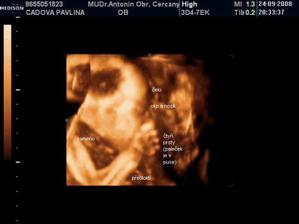

• 24.9.2008 – 4D ultrazvuk, potvrzena holčička